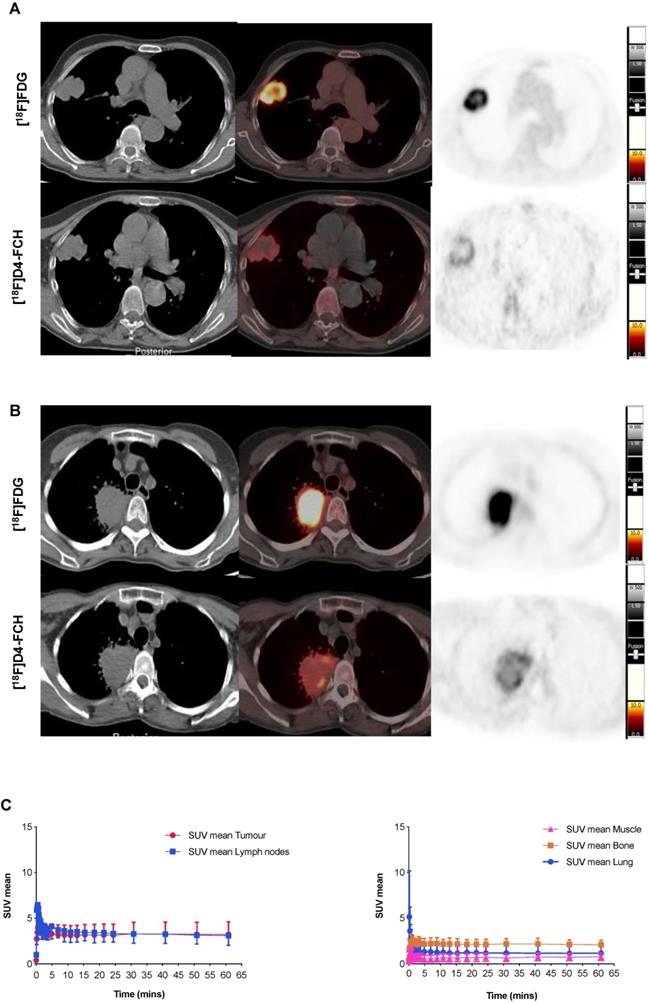

Images acquired with [18F]D4-FCH PET, and comparison to [18F]FDG PET are shown (Figures 2A and B). Mean decay-corrected time activity curves (TACs) for tumor, lymph nodes and normal tissues are shown in Figure 2C (SUV at 5, 30 and 60 min were similar, Table 2; Table S1). Physiological uptake of [18F]D4-FCH PET was noted in the salivary glands, liver, kidneys, pancreas and bladder. All primary tumors and involved lymph nodes were visible on [18F]D4-FCH PET/CT. NSCLC lesions were avid for both [18F]D4-FCH PET and [18F]FDG in patients who underwent [18F]FDG PET/CT as part of their staging work-up. [18F]D4-FCH derived uptake (SUVmax) in index primary lesions (n=17) ranged between 2.87 and 10.13; lower than that of [18F]FDG PET/CT (6.89 and 22.64) (Table 2; Table S1). On analysis of [18F]D4-FCH PET/CT (static) alone, the SUVmean and SUVmax values were higher in the lymph nodes and metastases compared with primary tumor in 7 out of 17 patients. Corresponding nodal lesions on [18F]FDG PET/CT (where available) showed in general, higher SUV values but in 1 patient (patient 3), SUV was found to be lower than that of [18F]D4-FCH PET/CT. The noted [18F]D4-FCH PET uptake within the mediastinal lymph nodes was negative for malignancy on correlation with surgical histopathology. It is unclear whether relevant or not, but on further investigation this patient was noted to be a heavy smoker. Unlike prostate cancer where low level symmetrical [18F]FCH uptake is often seen in reactive nodes [33], this was not seen with [18F]D4-FCH PET. The same number of lesions were noted with [18F]FDG PET/CT apart from 1 patient where [18F]FDG demonstrated uptake of a lower vertebral metastasis (patient 6).

Figure 2

[18F]D4-FCH and [18F]FDG Tissue uptake. (A) Axial views on CT, fused PET/CT and PET for diagnostic [18F]FDG and [18F]D4-FCH in a patient with squamous cell carcinoma of the right lung (patient 3 - see Table 2); (B) similar images in a patient with an adenocarcinoma of the right lung (patient 13 - see Table 2), SUV intensity threshold 0-10; and; (C) Mean decay-corrected time-activity curves (TACs) for normal tissue (normal lung, bone, including bone marrow, and muscle) and tumor and lymph nodes in dynamic PET imaging.